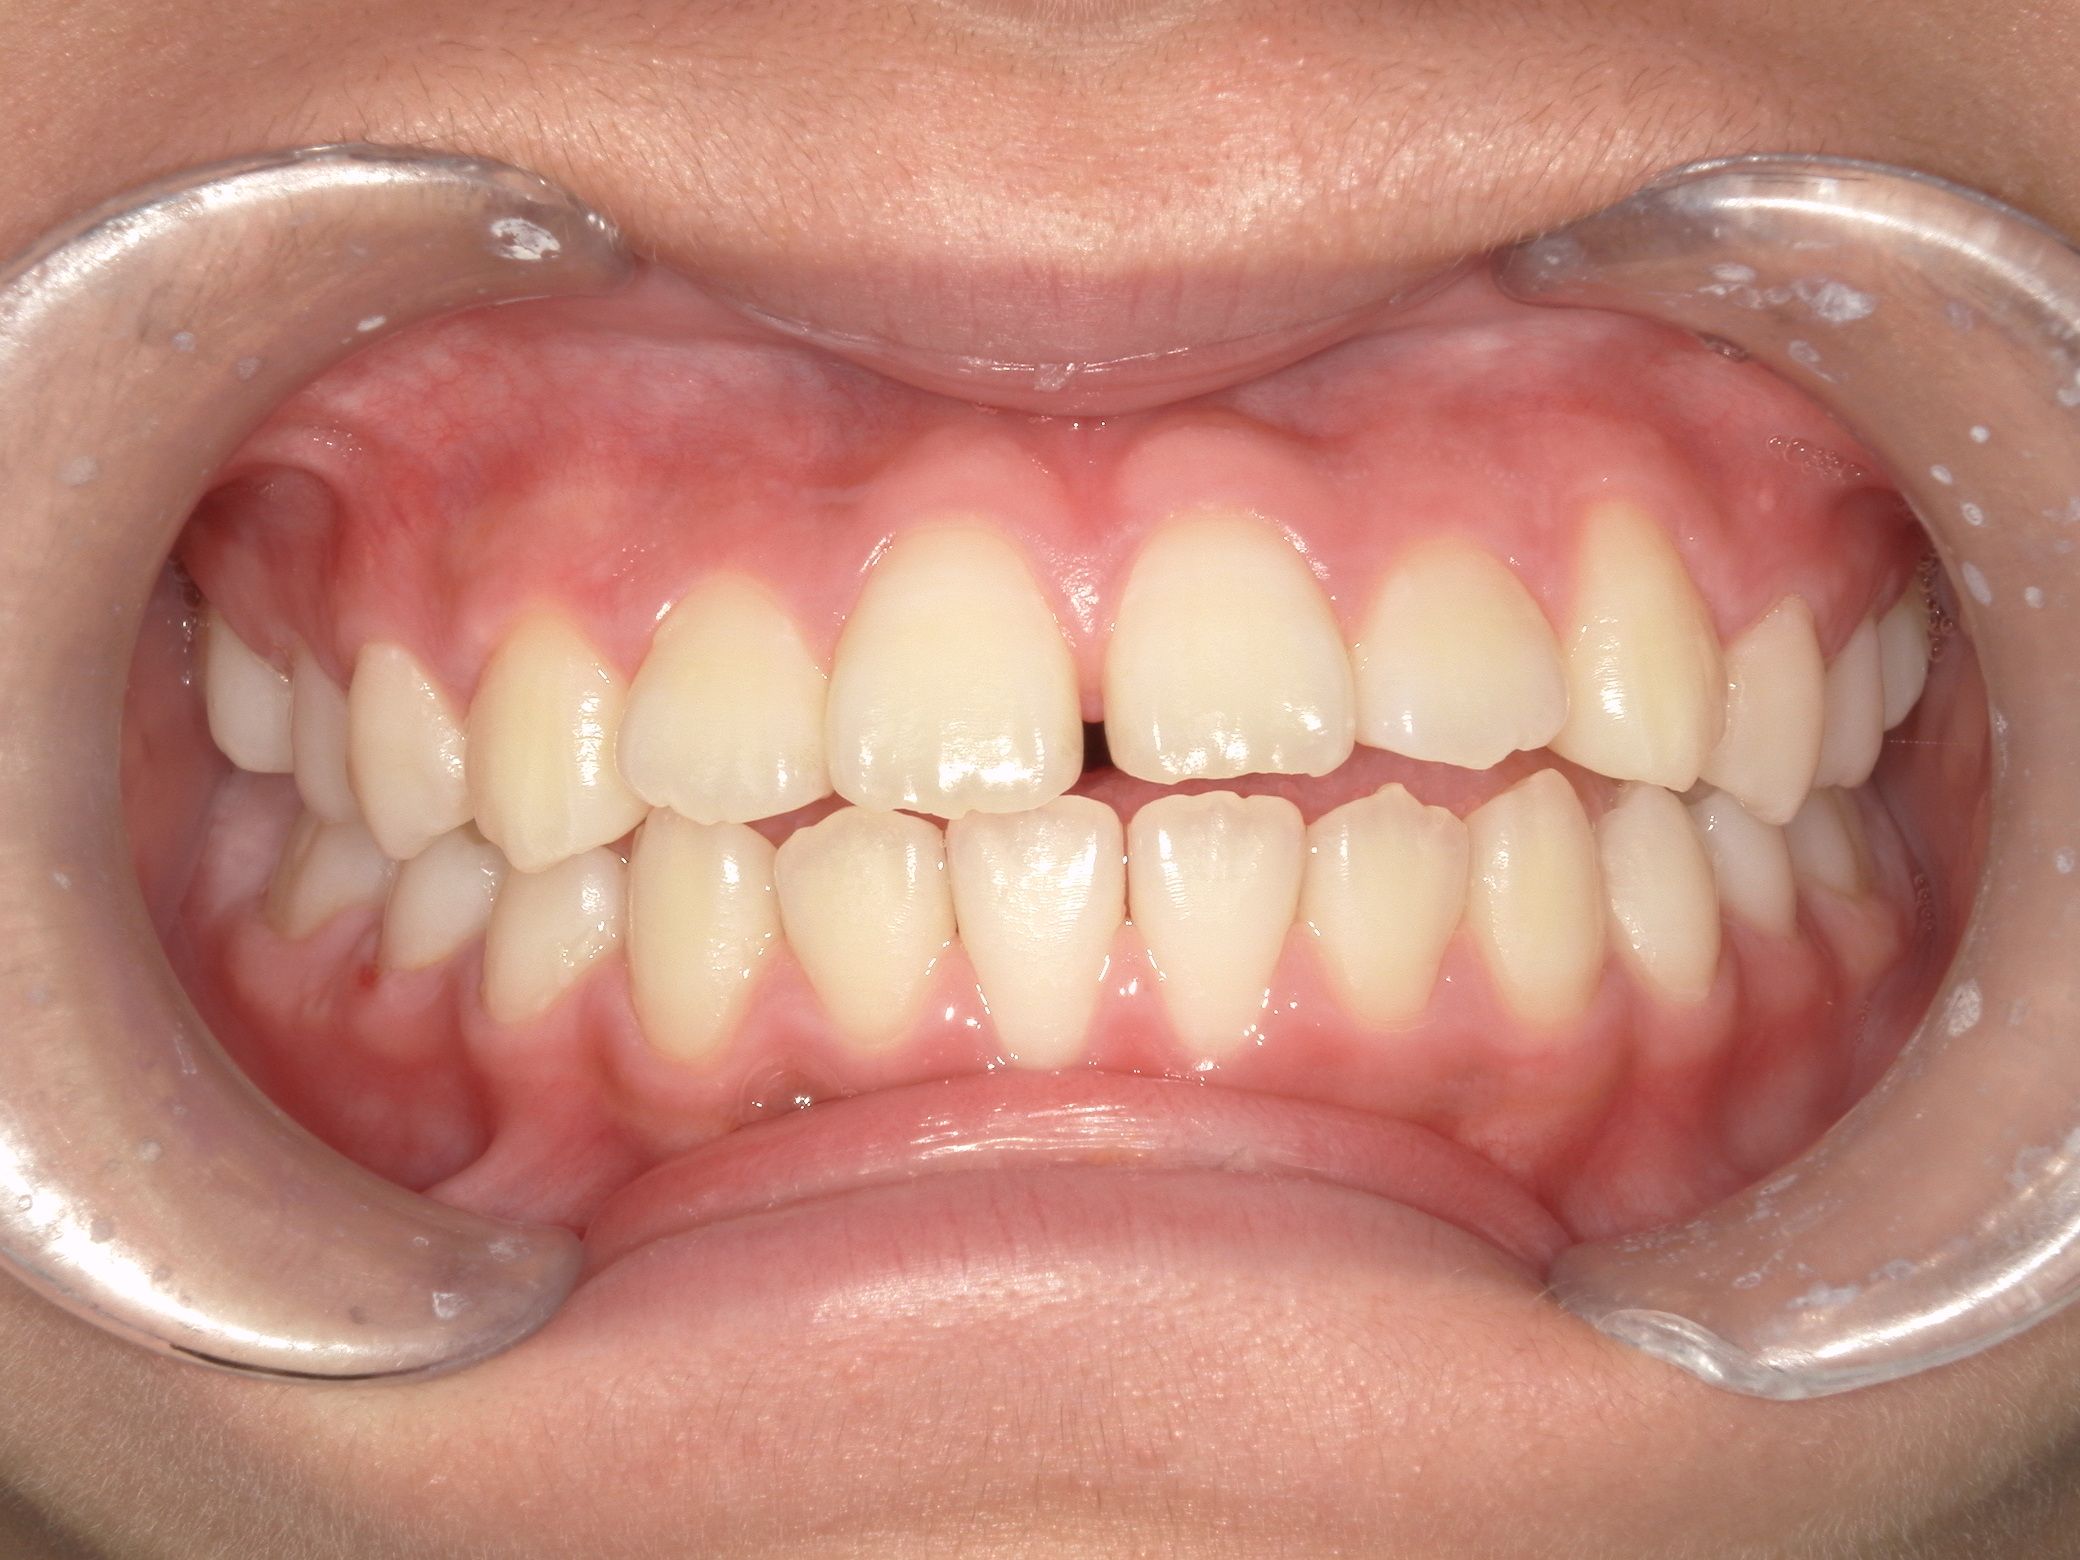

治療前 Before

上の歯並びがガタついています